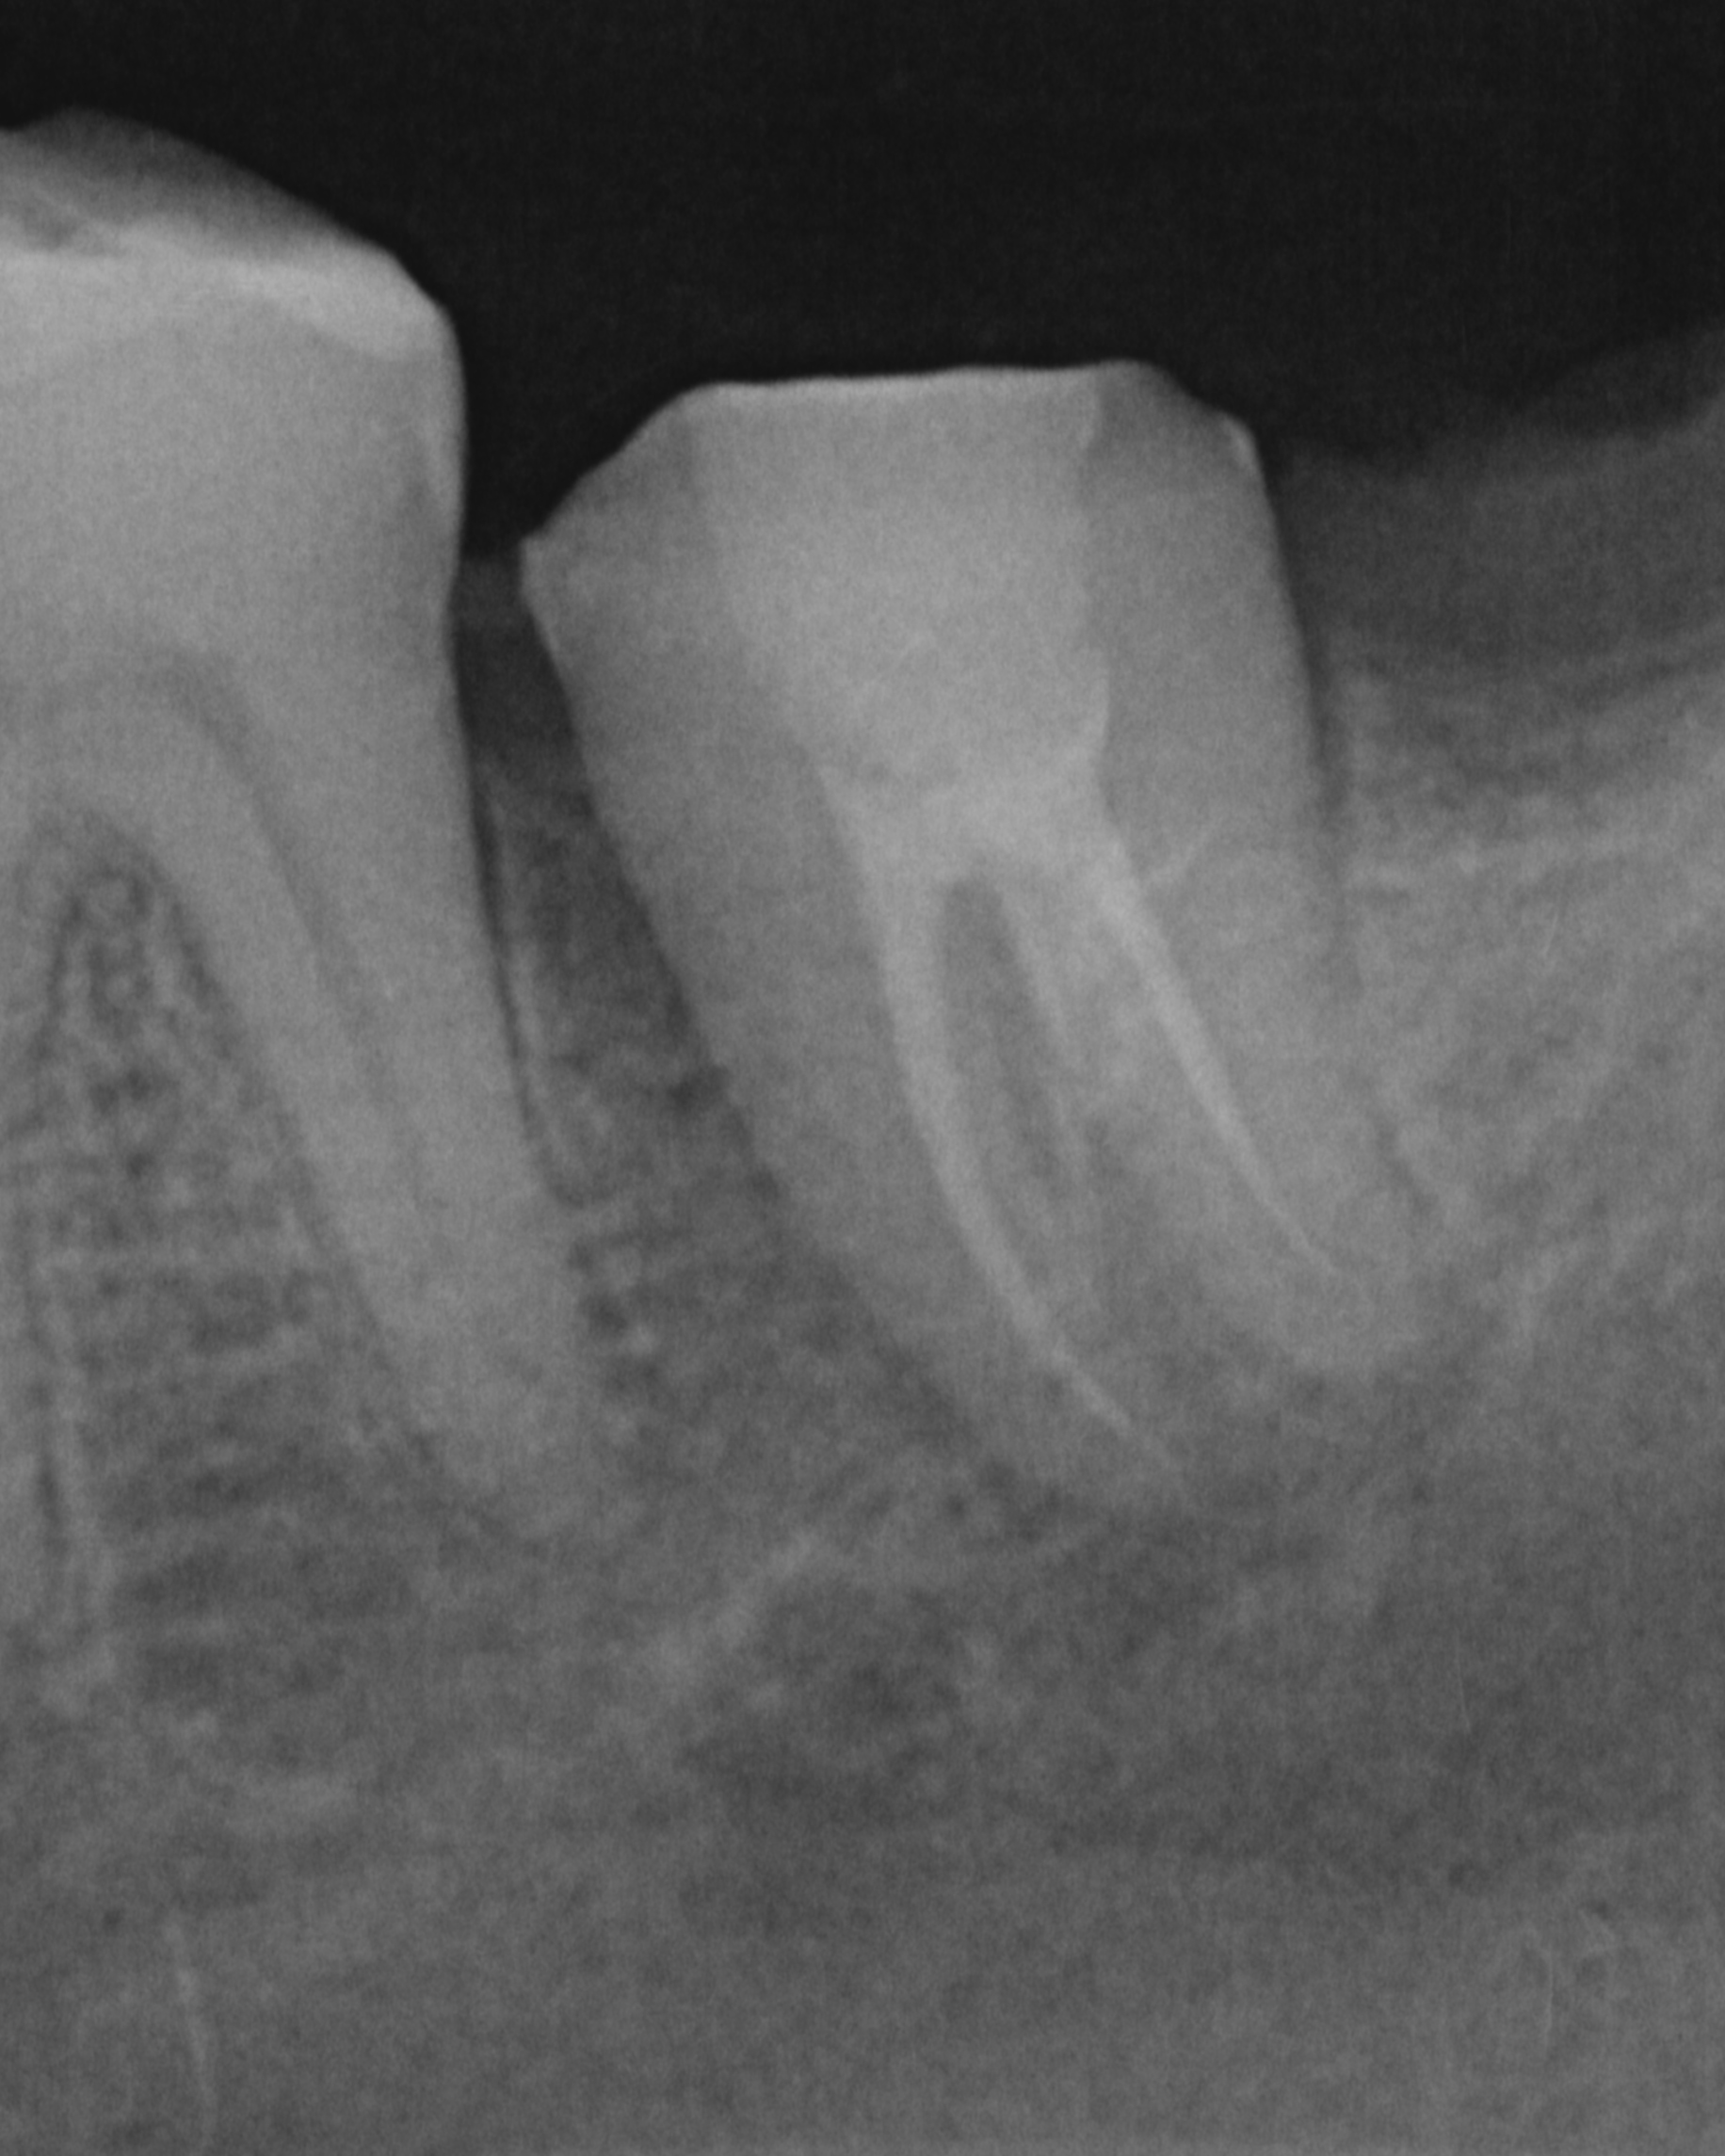

Perawatan saluran akar adalah salah satu perawatan yang berfungsi untuk menghilangkan atau memberhentikan sumber infeksi yang berkembang biak. Sering kali perawatan ini di sebut dengan perawatan saraf atau perawatan syaraf gigi, penggunaan nomenklatur ini dirasa kurang tepat. Tujuan lain dari perawatan saluran akar selain menghilangkan infeksi, perawatan saluran akar bertujuan mempertahankan gigi semaksimal mungkin didalam rongga mulut. Root Canal Treatment or Root Canal Therapy are The process of removing an infected, inflamed, or necrotic pulp and filling the residual space with an inert material. Access must first be gained to the pulp chamber and root canal system; the pulp canals are then measured and the pulp tissue and any infected material removed; the canals are then shaped, irrigated, and cleaned of debris; the root canals are obturated with a root filling material such as gutta-percha and a sealant, and finally a coronal seal placed to prevent bacteria from the mouth entering the root canal system. thank you for eighteeth dental and revoden asia using fast fill and fast pack to fiilling a root canals for more info you can visit my instagram https://www.instagram.com/furqan_rizal/ or contact my clinic +6281219972701